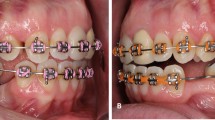

Twelve fresh maxillae containing the infrazygomatic crest regions from six body donors were collected. Sectional images of the maxillae specimens were acquired using µCT-80 (Scanco Medical, Bassersdorf, Switzerland). The X-ray settings were 55 KVp, 145 µA, and 8 W. The voxel size was 60.0 μm, and the integration time was 200 ms. These images were reconstructed in Mimics 19.0 (Materialise, Leuven, Belgium) to obtain the bone 3D model (Fig. 5a). According to the preset insertion trajectories, two mini-screws were inserted at the optimal and poor angulations into the infrazygomatic crest regions with similar cortical bone thickness on both sides of the maxilla from the same donor using the guide plates (Fig. 5b). The optimal and poor angulations to the bone surface were defined according to the results of the synthetic-bone test. These screw-bone specimens were scanned again using SmartScan to obtain screw-bone 3D models (Fig. 5c). The 3D models of screw-bone, mini-screw, and bone were also fitted in Geomagic Studio 2014. The SCA, STA, and EL were measured using the same method described in the synthetic-bone test.

Based on the results of the synthetic-bone test, the occlusogingival angulation of 30° is the poor angle and 50° is the optimal angle under each angle in the mesiodistal direction. Therefore, at each angle in the mesiodistal direction (60°/75°/90°), two maxillae were respectively assigned for the occlusogingival angulation validation test.

The differences between the poor and optimal angulations are shown in Fig. 7. Statistically significant differences were observed between the two groups in LPS (P = 0.011), SCA (P = 0.020), STA (P = 0.004), and EL (P = 0.001).

The differences between the optimal and poor angulations in cadaver-validation testing. (a) The difference in the LPS. (b) The difference in the SCA. (c) The difference in the STA. (d) The difference in the EL. LPS lateral pull-out strength; SCA screw-cortical bone contact area; STA screw-trabecular bone contact area; EL exposure length